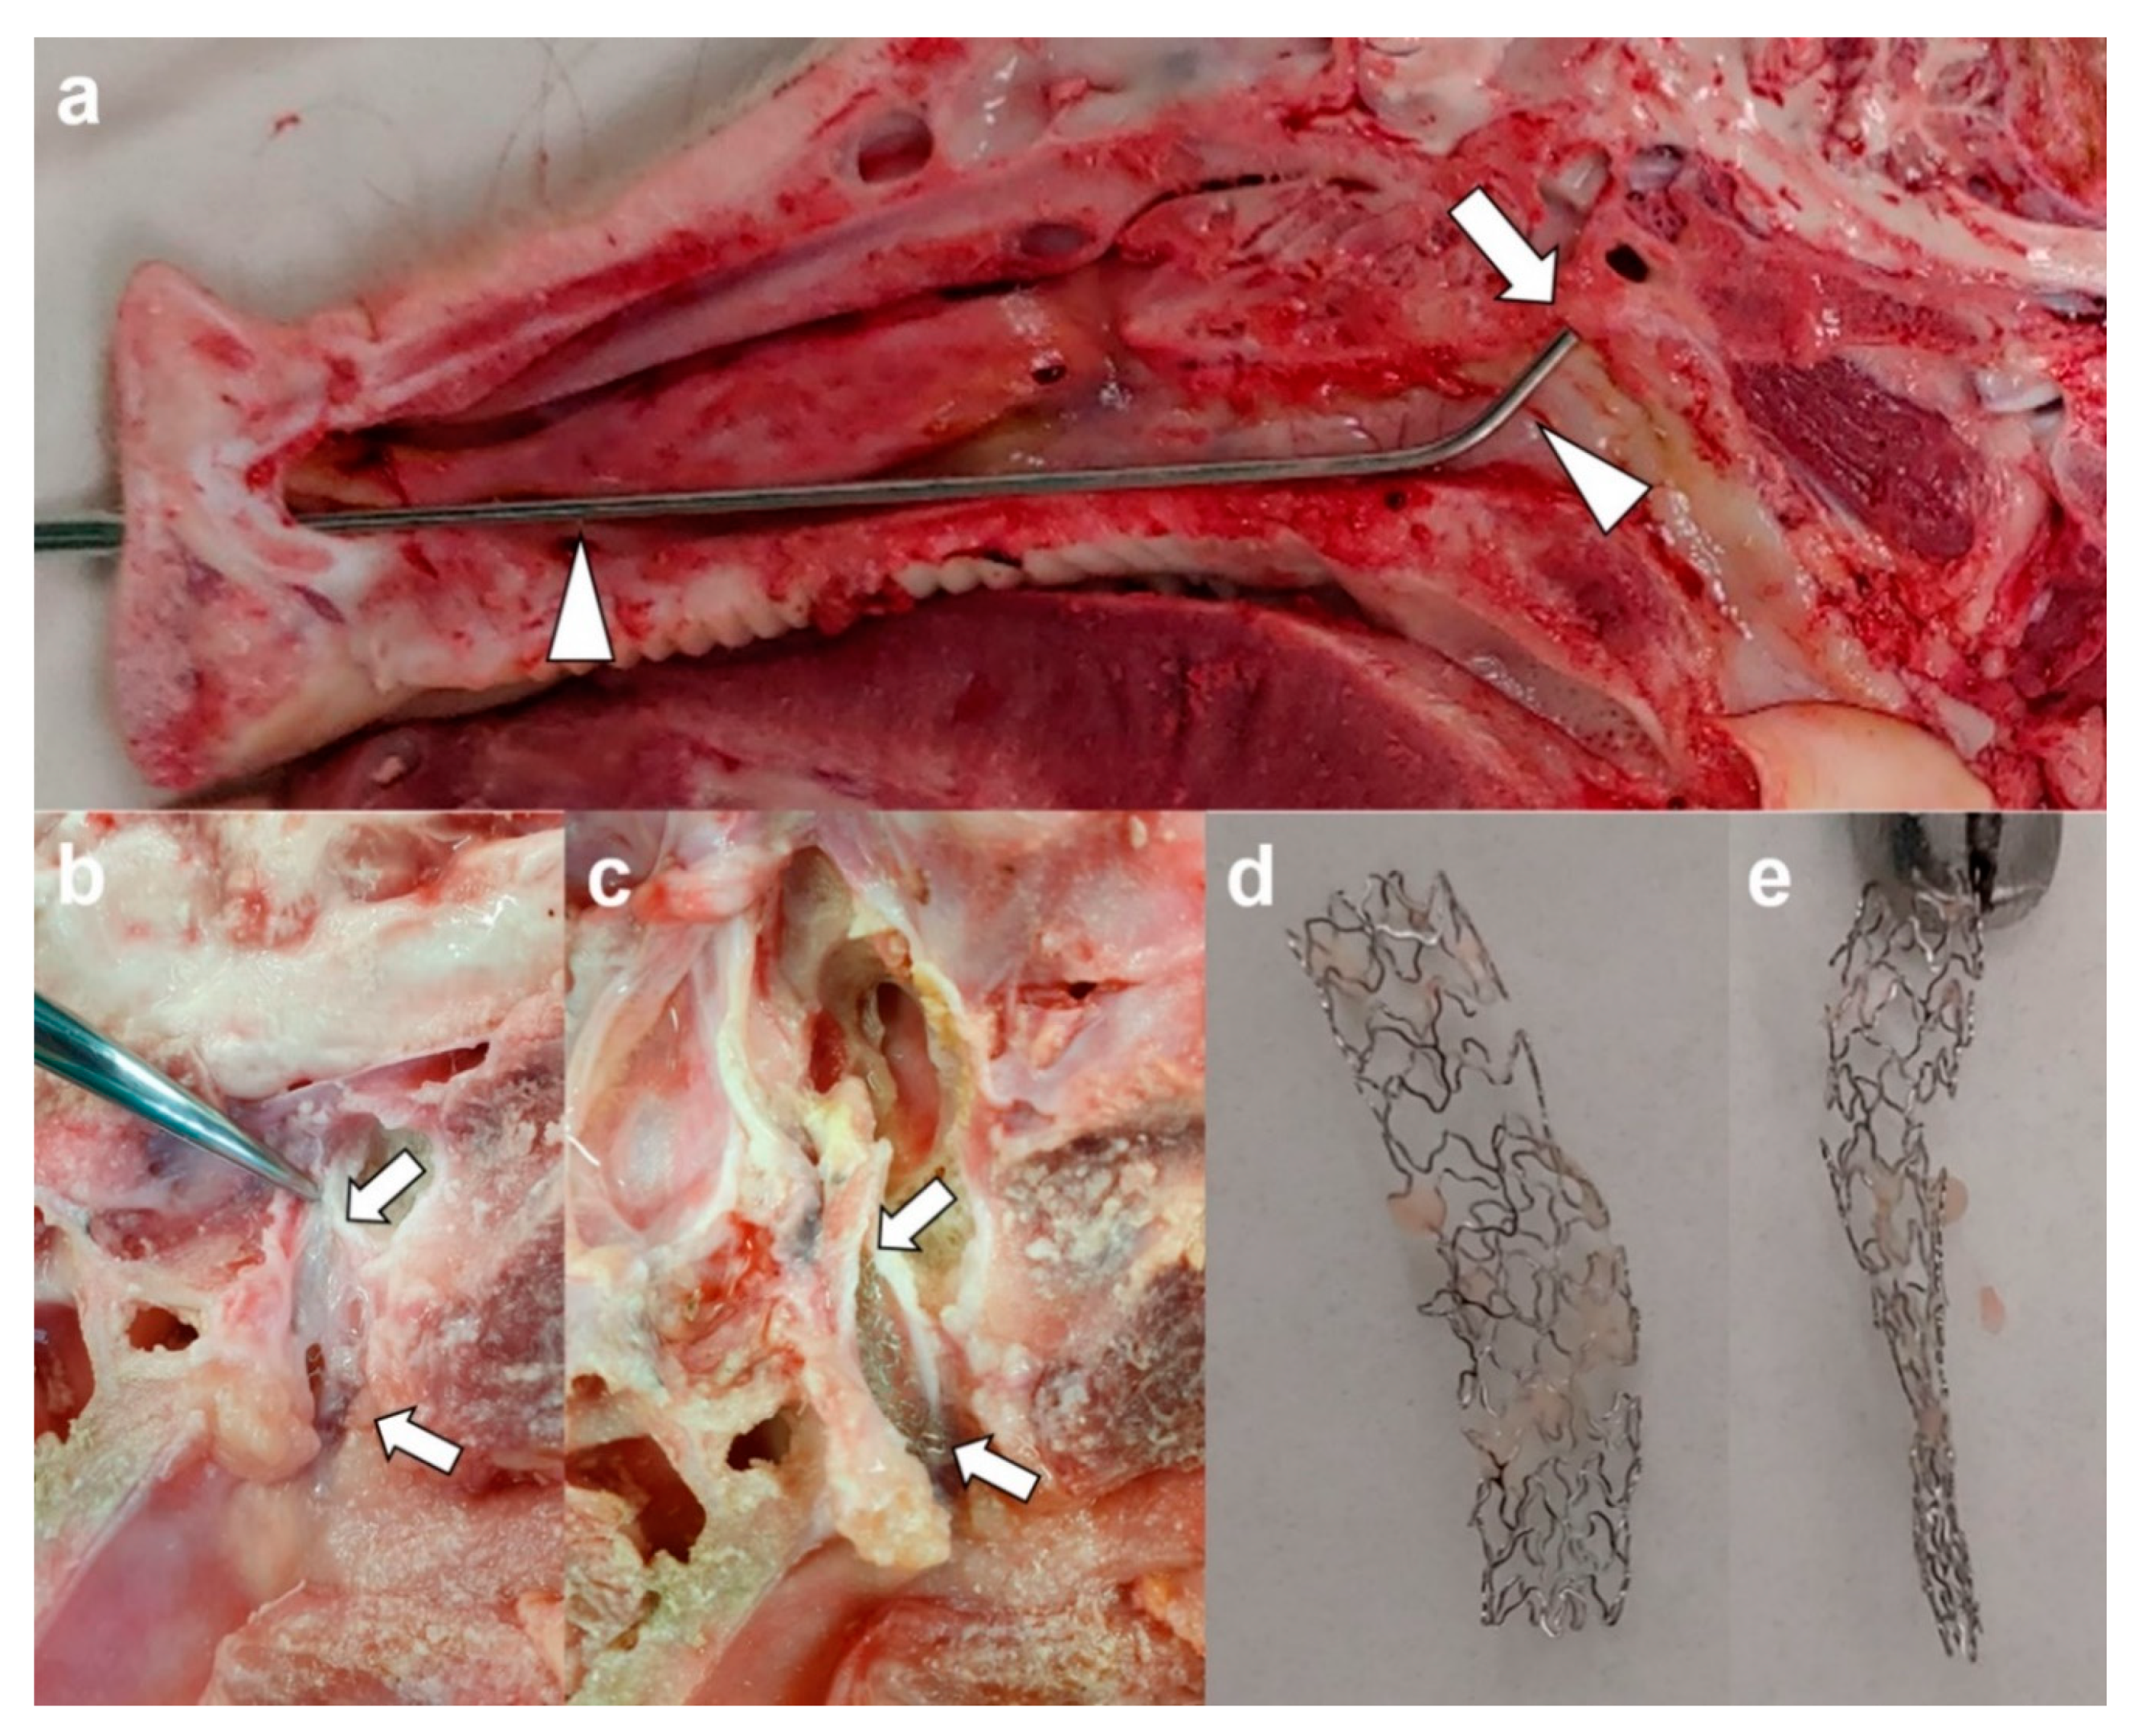

2.5. Gross and Histological Examination